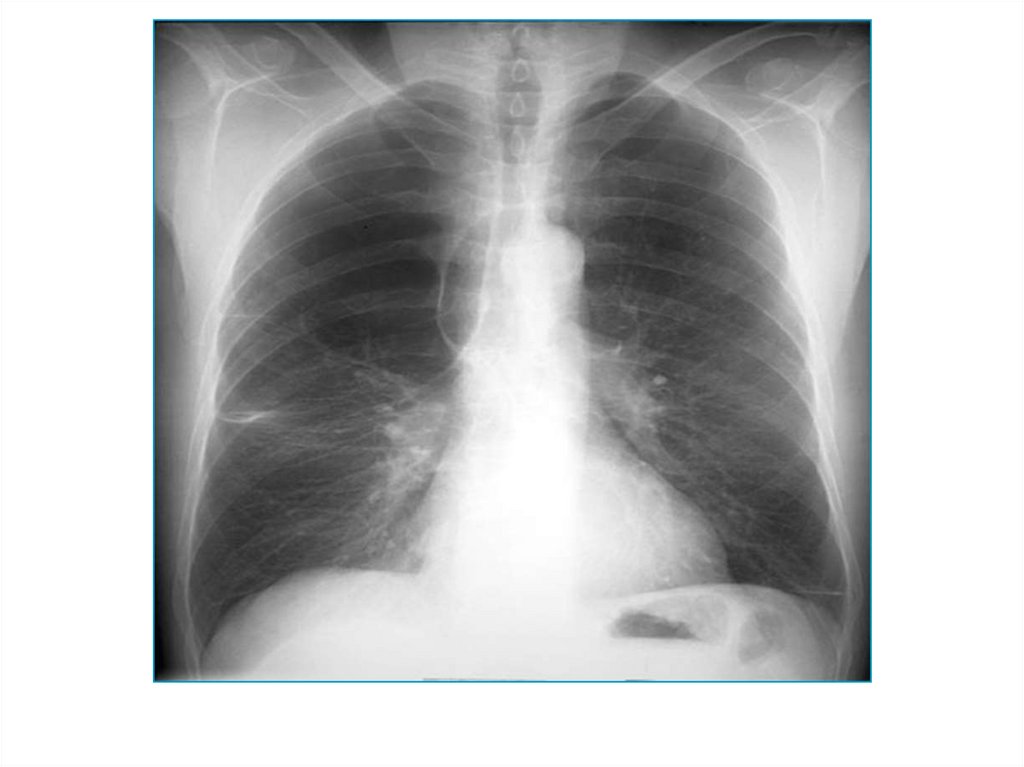

13. Уменьшение притока крови

Причина - гиповолемия малого круга

кровообращения при некоторых врожденных

пороках сердца (тетрада Фалло,

изолированный стеноз легочной артерии).

Видимая картина – двустороннее тотальное

просветление над всеми легочными полями.